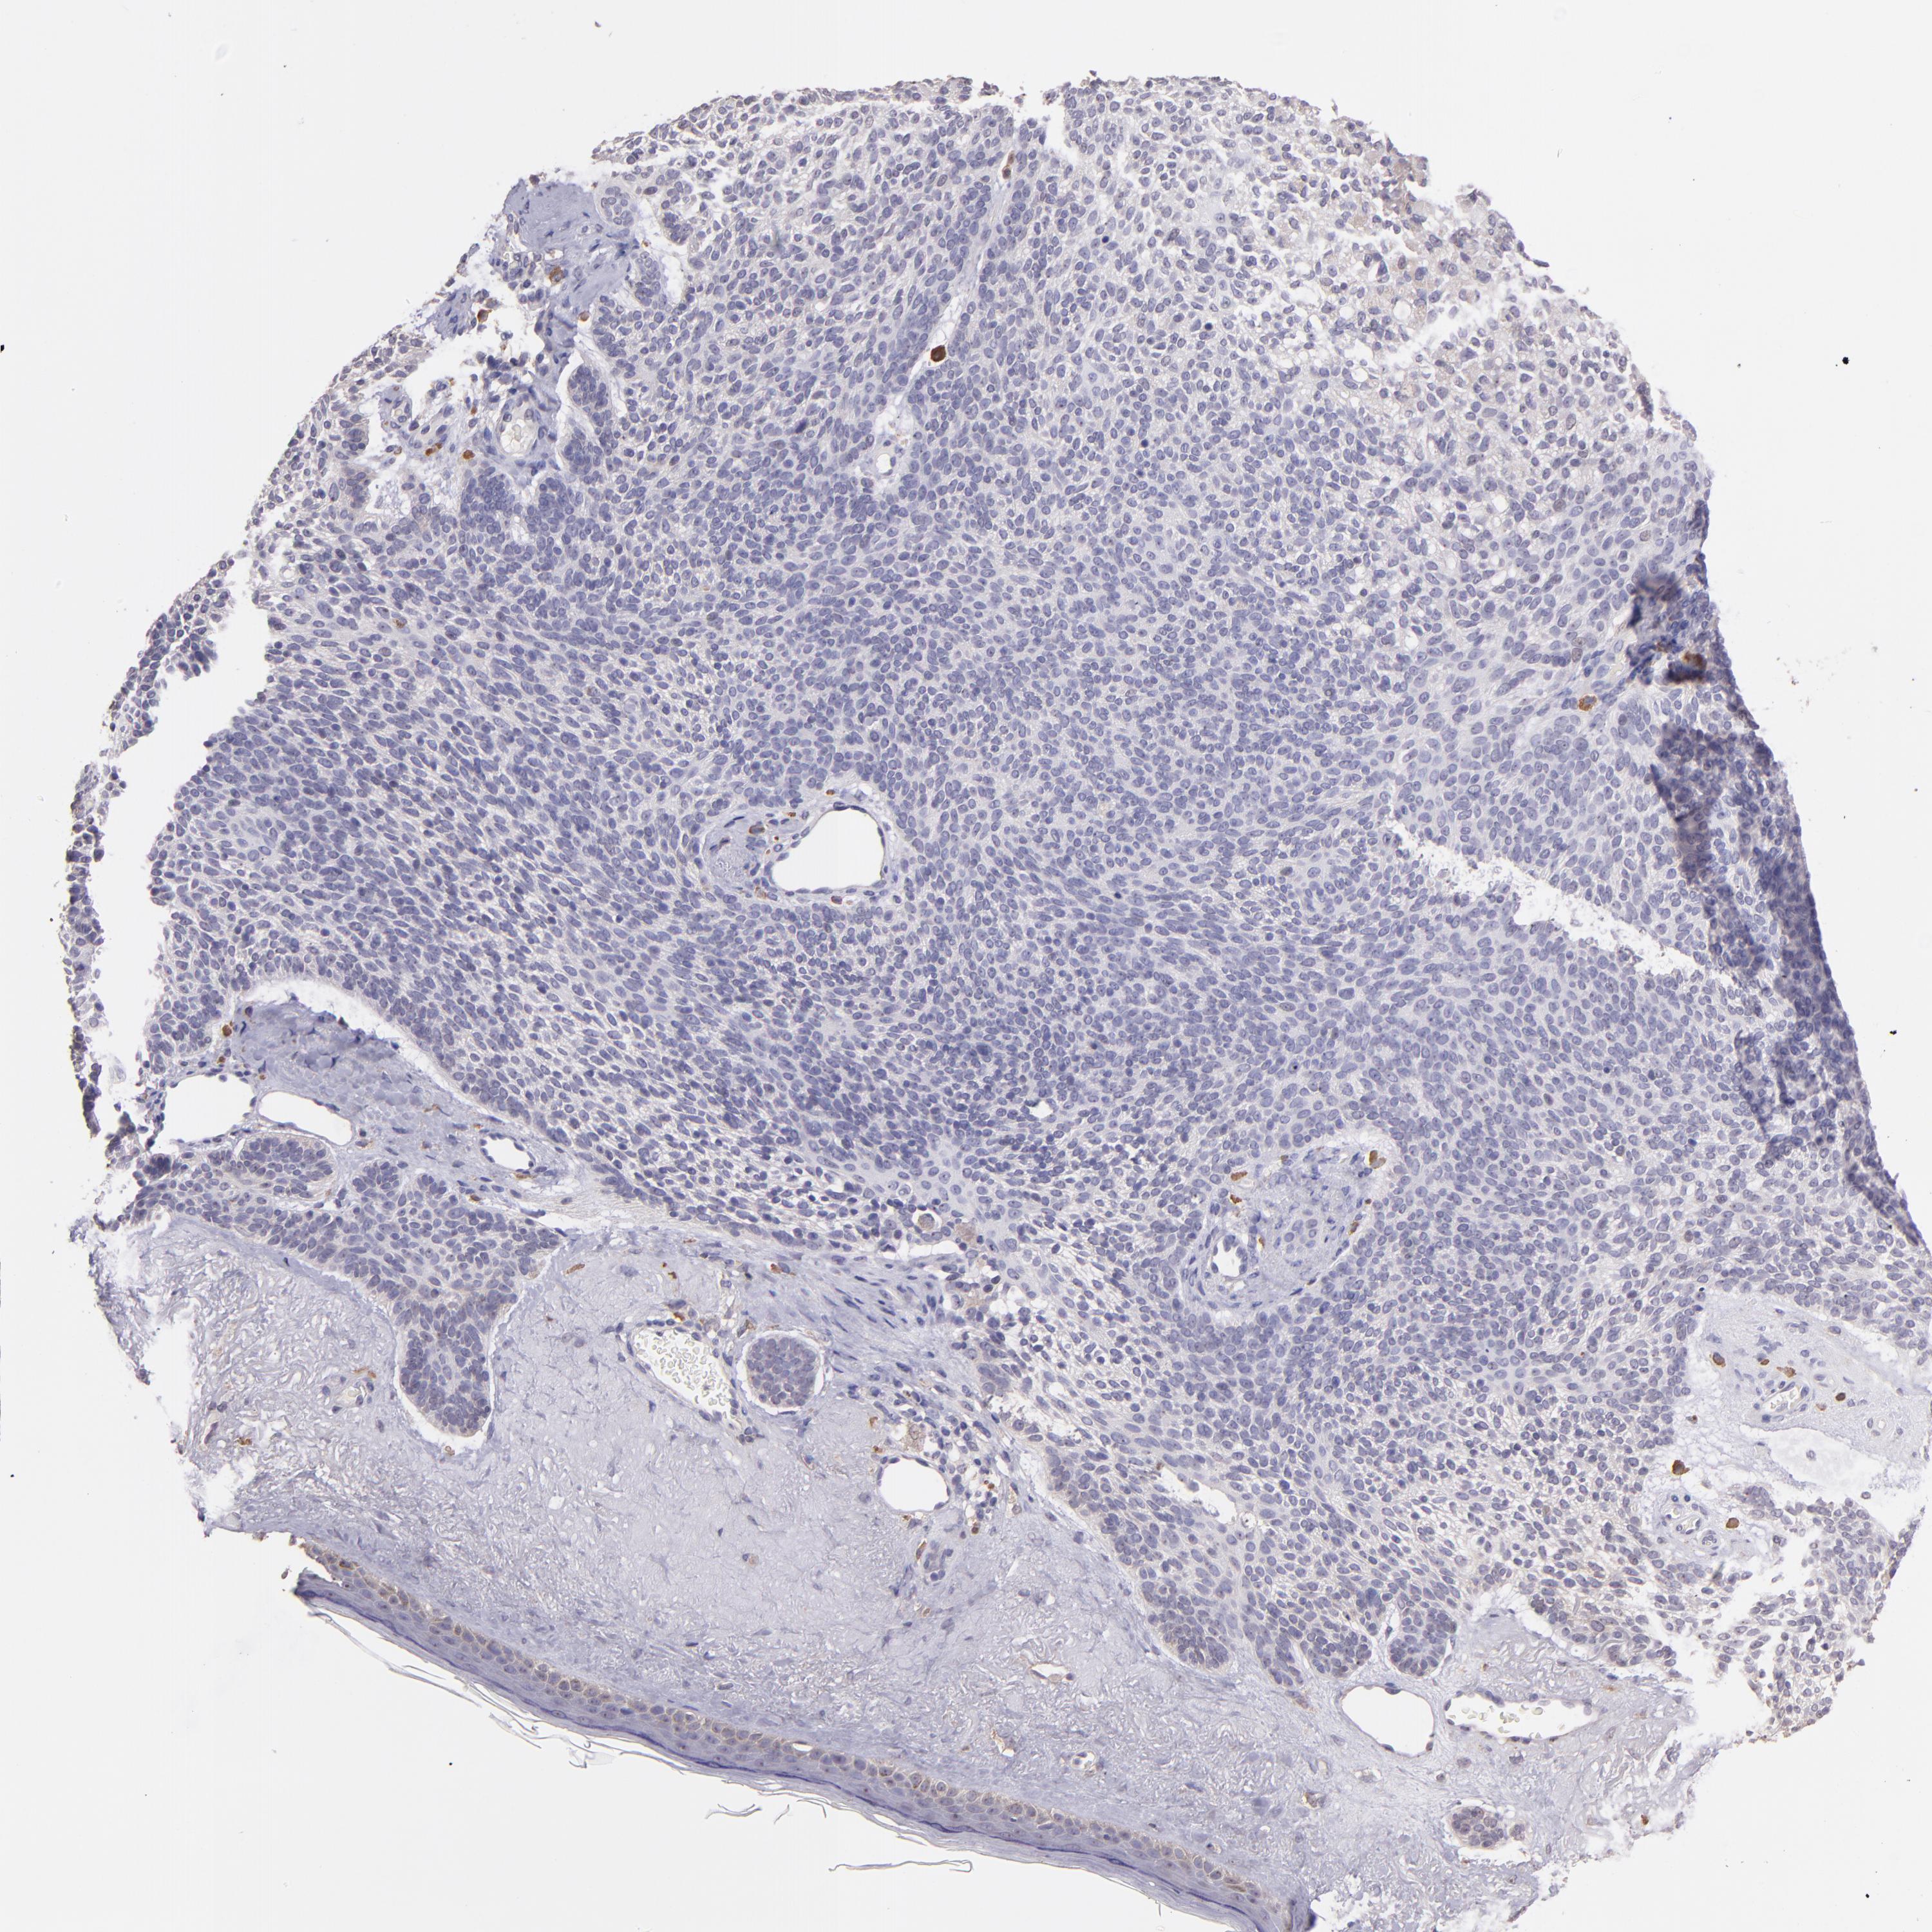

CANCER SKIN CANCER Show tissue menu

Basal cell and squamous cell cancer

SKIN CANCER - Protein expressioni

A mouse-over function shows sample information and annotation data. Click on an image to view it in a full screen mode. Samples can be filtered based on level of antibody staining by selecting one or several of the following categories: high, medium, low and not detected. The assay and annotation is described here.

Antibody stainingi

Antibody staining in the annotated cell types in the current human tissue is reported as not detected, low, medium, or high, based on conventional immunohistochemistry profiling in selected tissues. This score is based on the combination of the staining intensity and fraction of stained cells.

Each image is clickable and will lead to virtual microscopy that enables deeper exploration of all samples and also displays staining intensity scores, fraction scores and subcellular localization as well as patient and tissue information for each sample.

Antibody HPA001667

Antibody CAB016724

Staining

Squamous cell carcinoma, NOS

Basal cell carcinoma

Squamous cell carcinoma, metastatic, NOS